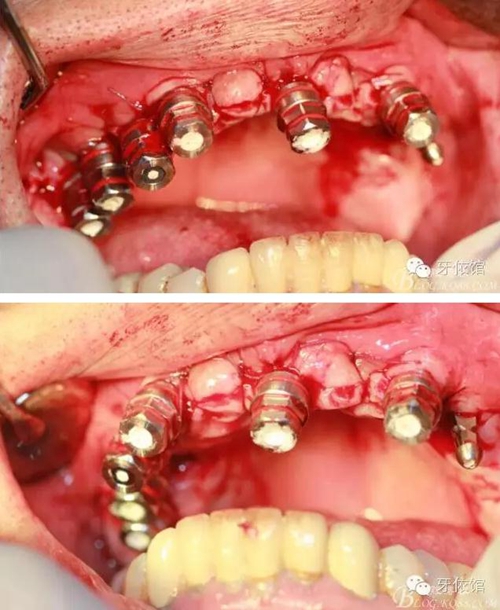

縫合

取模型

安置愈合基臺

第二天患者來帶臨時(shí)冠口內(nèi)情況,患者沒有絲毫腫脹

戴入臨時(shí)冠

的確,切牙孔神經(jīng)破壞后患者口內(nèi)感覺似乎沒有任何異樣,當(dāng)然此患者較易滿足,我不排除如果遇上一個(gè)心思縝密個(gè)患者,是否他也會這樣感覺沒有變化。